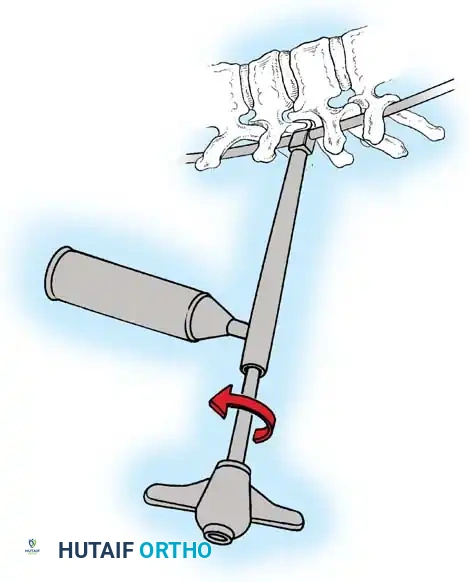

In the lumbar spine, the facet joints are oriented in a more sagittal plane, necessitating a modified approach.

Fig. 38-27: The Moe technique adapted for lumbar facet fusion, addressing the sagittal orientation of the joints.

- Utilize a small osteotome or a needle-nose rongeur to resect the adjoining joint surfaces.

- This creates a distinct rectangular defect within the sagittally oriented joint space.

- Pack this defect forcefully with cancellous bone graft.

- Proceed to decorticate the entire exposed posterior elements (laminae and transverse processes) using Cobb gouges, always directing force away from the spinal canal.